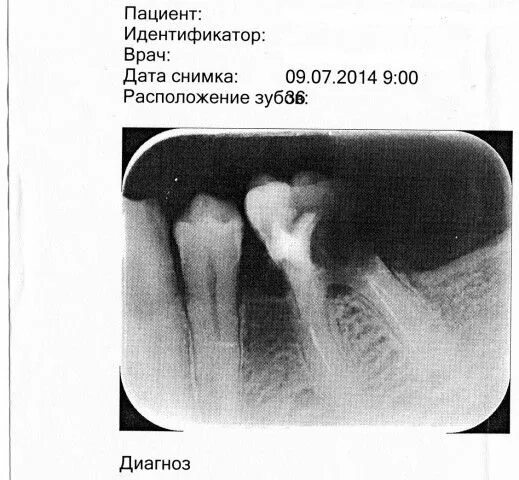

Дата снимка